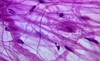

nautral course of disease chart